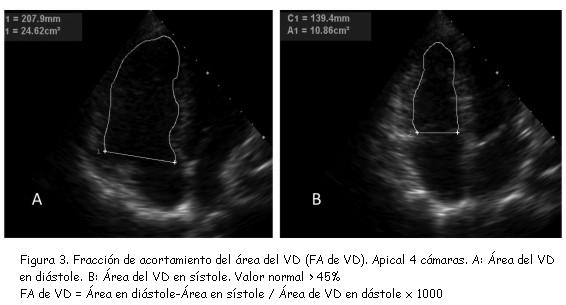

1) Fracción de acortamiento del área del ventrículo derecho

Este parámetro (figura 3) mostró excelente correlación (r = 0,80; p < 0,001) con estimaciones de la fracción de eyección del VD realizadas mediante RNM(30).